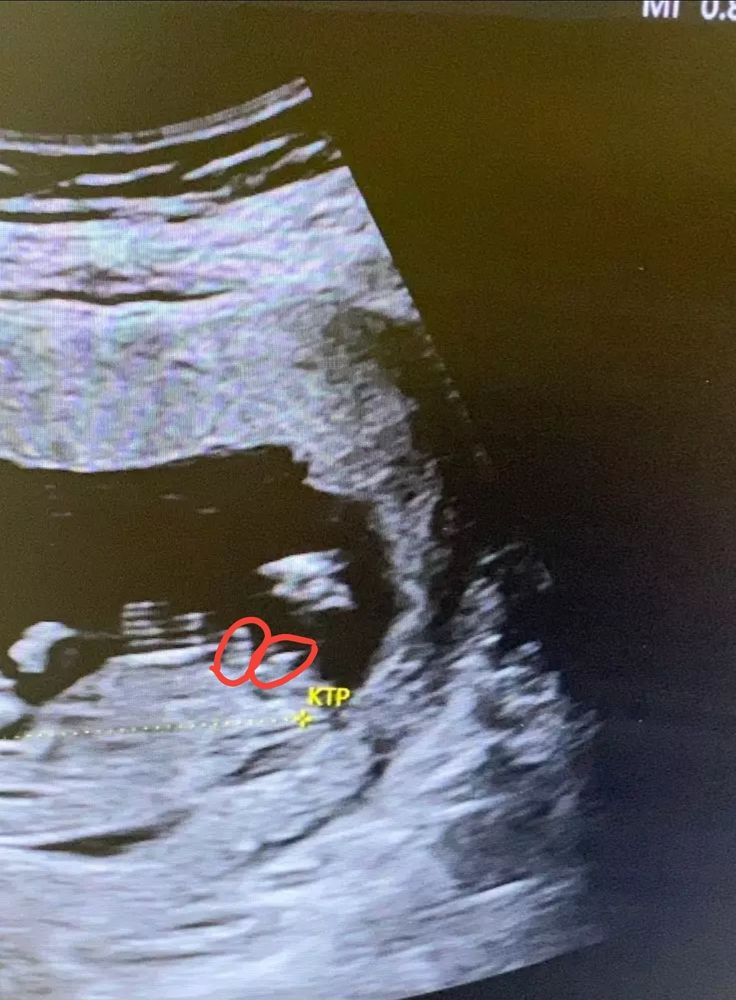

Изображение 50 на 50)) что-то из этих двух может быть половой бугорок)

Ольга , 😅 будем ждать следующее узи ))

Ольга , скажите через неделю кто у Вас, у нас похожий половой бугорок 😄